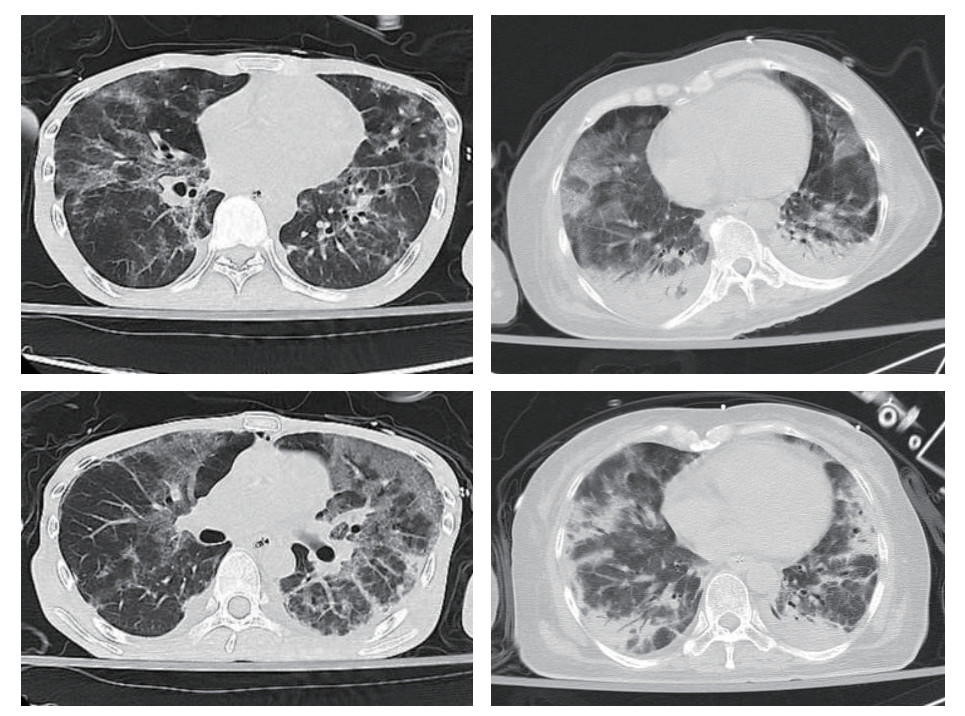

2 结果 2.1 基本情况比较本研究初步纳入50例PCP确诊病例,其中排除4例HIV阳性病例,最终有46例HIVn-PCP病例纳入研究。其中男性24例(52.00%),女性22例(48.00%),年龄(56.43±14.47)岁,总病死率为47.83%(22/46)。大部分患者都有长期应用皮质激素(25/46,54.35%)、应用免疫抑制剂(13/46,28.26%)或放化疗(16/46,34.78%)等病史。主要临床表现为呼吸困难(40/46, 86.96%),发热(39/46,84.78%),咳嗽和(或)咳痰(29/46, 63.04%),胸部影像学表现均有磨玻璃影(46/46, 100%,图 1),其次为胸腔积液(20/46, 43.48%)及肺实变(9/46, 19.57%)。

| 图 1 HIVn-PCP患者胸部CT:两肺多发斑片影及磨玻璃影,两下肺实变 |

本文通过对46例HIVn-PCP患者的临床资料进行分析,研究结果发现,这类患者合并自身免疫性疾病占47.8%,恶性肿瘤占39.1%,其住院期间病死率高达47.83%。这些患者的临床表现以呼吸困难(86.96%)、发热(84.78%)和咳嗽(63.04%)等为主要表现,胸部影像学表现均有磨玻璃影,与既往PCP相关研究结果相似[7-8]。除此之外,死亡组平均年龄及BMI均高于生存组,年龄越大, 免疫功能减退更明显, 更易发生感染且更严重,最终预后相对更差。在一个关于免疫功能低下的成人PCP研究中亦有发现,年龄、BMI等指标与这些患者住院病死相关[9]。